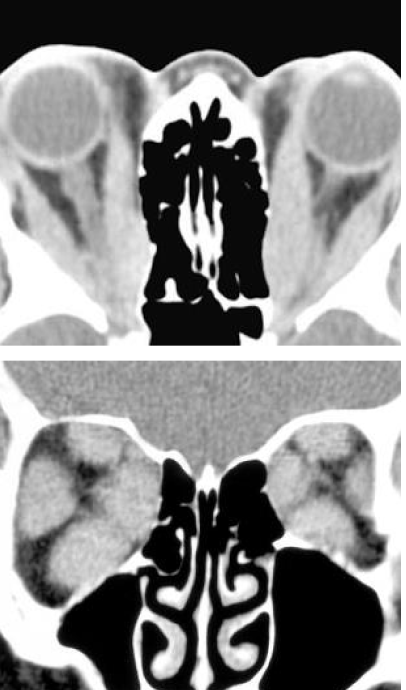

What does this image suggest?

A

Graves orbitopathy (big eye muscles, bulging eyes)

What condition does this image suggest?

Graves orbitopathy

43

What is Graves orbitopathy?

A thyroid eye disease that causes soft tissue swelling and scaring that can lead to proptosis, double vision, and vision loss (compressed optic nerve)